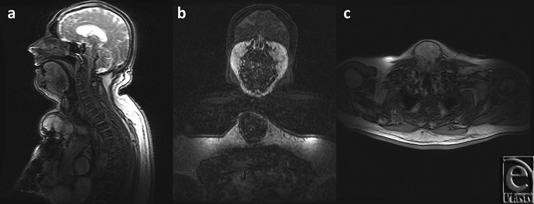

A thorough work-up ensued yielding further details of the mass, as noted on the CT scan (Fig 2) and magnetic resonance imaging (Fig 3), which established this as a 8.4 × 6.2 × 8.6 cm3 complex solid tissue mass within the lower neck arising from the sternal manubrium, with extensive bone destruction. Because of the clinical and radiological appearance, a provisional diagnosis of a sternal granuloma was made.

The CT-guided biopsy showed cells of uncertain significance, and the aspirate demonstrated no abnormal growth. The patient was then scheduled for an elective excision of the mass. During the procedure, an 8.5 × 8.5 × 2.5 cm3 mass arising from the anterior portion of the sternal manubrium, extending to the neck and locally invading the skeletal muscle was partially resected (Fig 4). A complete excision could not be performed because of the high-risk location of some parts of mass as well as the patients overall suboptimal health condition. A conclusive diagnosis could not be reached on frozen section at the time of surgery. Therefore, the resection entailed removing all visible aspects of the mass.